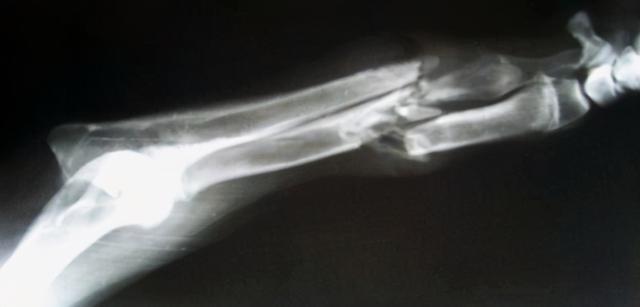

警方又惊奇地发现车里死者身上骨头多处粉碎骨折,由于车辆是翻入沟里,但是沟底距离路面不足1米的距离,车辆翻滚也不至于能使驾驶员多处粉碎骨折,警察确认这属于他杀并放入车里,然后点燃车辆烧毁证据。